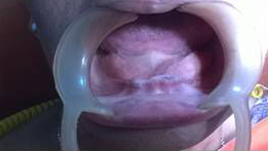

Use of Bone Graft & GTR membrane for an Implant

Suturing after Bone Grafting

After 6 months